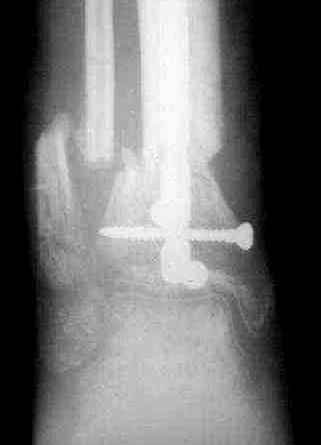

5. Ну и чтобы не быть голословным. Молодой человек подорвался на фугасе (Чечня, 2005 год). Свежие рентгенограммы:

Соответственно ожоги и дефект мягких тканей, переломы костей стопы и пр. Наложили аппарат

Илизарова (как придется), хирургически обработали и героически заживляли мягкие ткани с многочисленными кожными пластиками. В итоге через полгода я принял его вот таким:

Реализовал описанную выше методику, и в итоге вот что получилось. Высылаю лишь прямые проекции,

в боковых тоже всё в тему.

Очень пригодились карбоновые кольца (Джолдас -огромное спасибо, я твой должник!!!), поскольку остеопороз дистального отломка был просто невероятный. На цифровом рентгене с трудом угадывались контуры.

Рентген в процессе перемещения - внизу карбоновые кольца, тракция фрагмента спицами с упором.

внешний вид в аппарате - не завершающем этапе, сначала стопа тоже была фиксирована в аппарате.

Сейчас аппарат сняли, но случай ещё не завершенный.

Признаюсь честно, не совсем уверен в прочности консолидации на стыке косточек. Кроме того, укорочение в районе 6 см. Сейчас реабилитация - ходит опираясь на ногу с одним костылем.

Продолжение, видимо, будет... Возможно, будем удлинять.